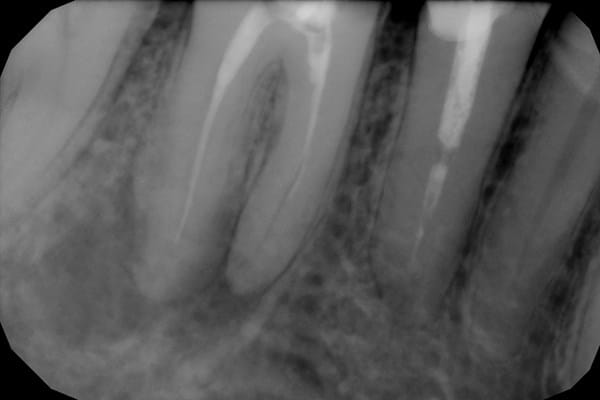

Hace 4 años me hicieron una endodoncia en Méjico no muy bien hecha, desde las primeras semanas me dolía un poco, la reconstrucción fue hecha en España pero al cabo de dos años empezó a fallar. Ahora me han hecho unas radiografías y me dicen que se una infección. Me comentan que la reendodoncia es complicada porque hay que quitar la que está hecha, esperar a que se desinfecte, volver a hacer la endodoncia y reconstrucción muy complicada debido a que la caries empezó muy abajo y pone una funda. Y es posible que aun así falle, así que me recomiendan un implante. Pongo las imágenes (es un molar abajo a la izquierda).

Respuesta